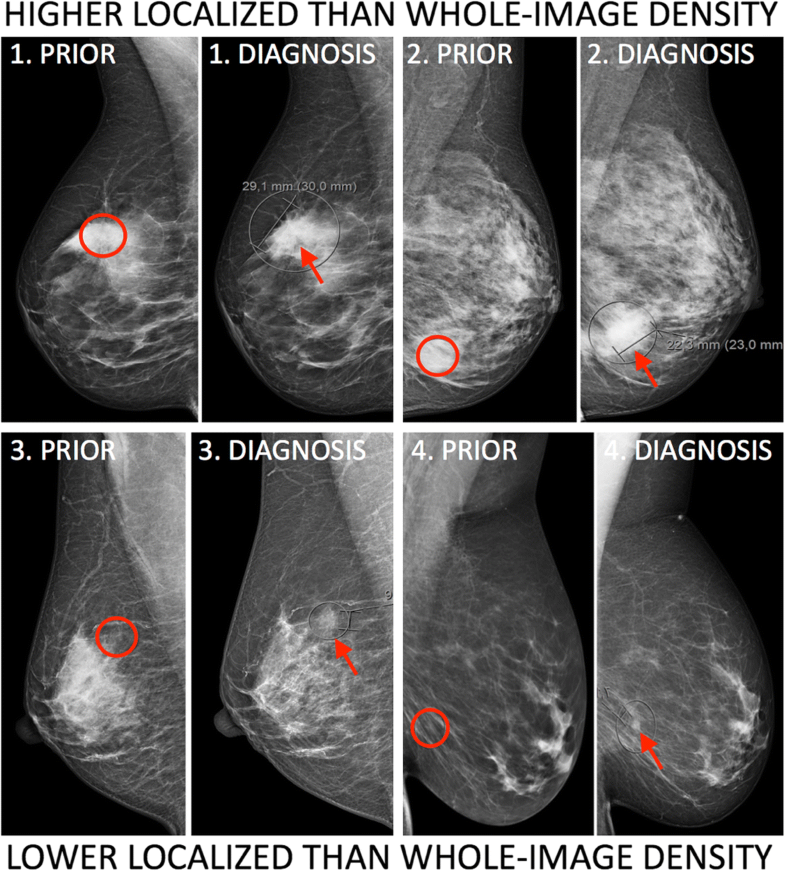

From breast-cancer-research.biomedcentral.com

Localized mammographic density is associated with interval cancer and Radiology Mammogram Breast Density Only a radiologist looking at a mammogram can tell if a woman has dense breasts. Breast density assessment is an important component of the screening mammography report and conveys information to referring clinicians about. Breast density is a proportional measure of the glandular, connective and fatty tissues within a woman's breasts. The only way to know if you have dense. Radiology Mammogram Breast Density.